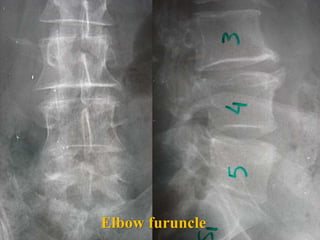

4th case

D.N.

M 61– Cardiologist

Symptoms

 Severe Neurologic deficit

 Intensive Thoracic-lumbar Pain

 High fever

Laboratory

 Neutroph. ↑

 SR 60

PMH

 Heavy smoker

 Diabetes melitus

 Recent Elbow Furuncle (untreated)

Elbow furuncle